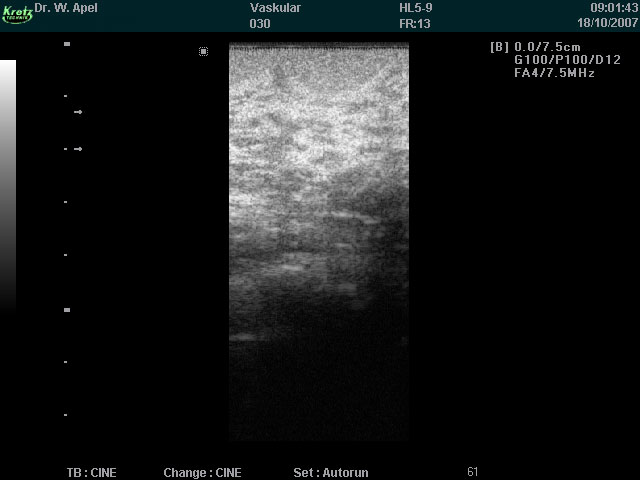

Ultraschall in der Gynäkologie (Brust)

Die Sonographie der weiblichen Brust ist eine strahlungs- und schmerzfreie Untersuchung.

Basierend auf der Ultraschalltechnik ermöglicht sie eine bildliche Darstellung des Brustgewebes.

Neben der Mammographie und Kernspintomographie besteht durch die Ultraschalluntersuchung eine weitere Möglichkeit Veränderungen im Gewebe der Brust frühzeitig zu entdecken und gegebenenfalls therapeutische Maßnahmen zu ergreifen.

In der Hand des erfahrenen Untersuchers eignet sich die Brustsonographie besonders gut zur Beurteilung der jugendlichen Brust, die durch dichtes Drüsengewebe gekennzeichnet ist.